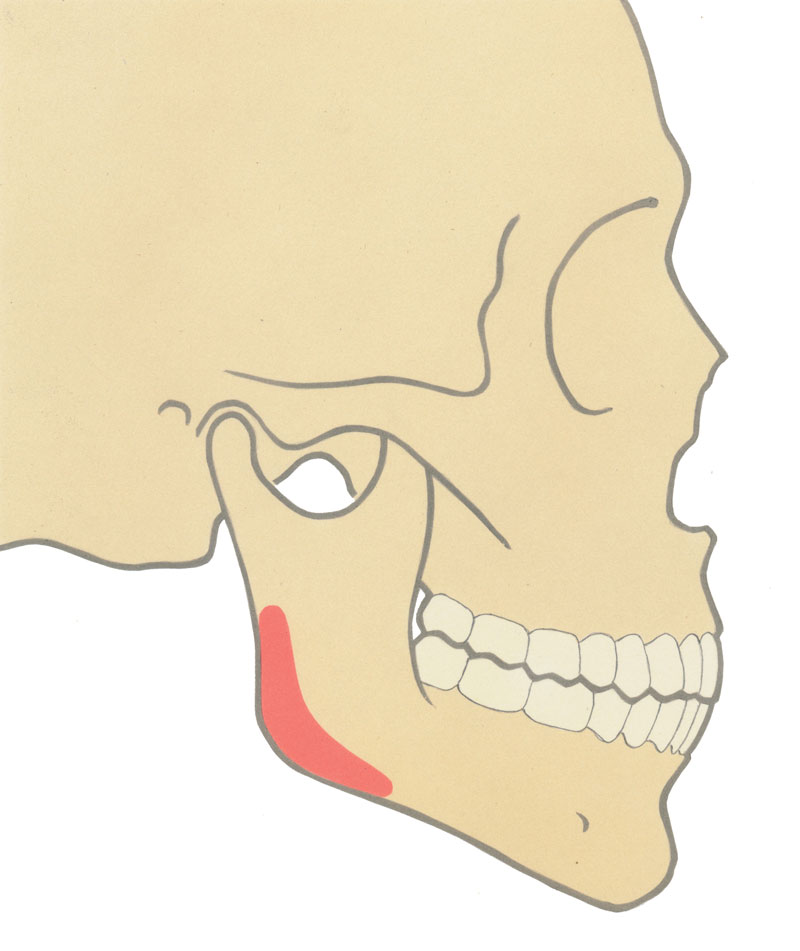

The mean angle in males is 128° (+/- 2.36°) and in females, 126° degrees (+/- 2.41°) [2]. Interestingly, the mean values are uniform for both sexes but the angle is subject to bias. A relatively short vertical or horizontal mandibular component may result in an obtuse angle (Figure 1). Contemporary literature addressing the transverse relationship is limited. In the frontal view, the mandibular angle is influenced by skeletal form, masseteric muscle volume and the overlying skin drape. There is a growing trend among female actresses, such as Olivia Wilde and Angelina Jolie, to show a relatively wide intergonial distance. These subtle facial traits are steadily filtering down to the desires of patients and the shape of the mandible is becoming an increasingly important gender determinant and makes the sole reference of the gonial angle obsolete.

Figure 1: a) Normal projection.

Figure 1:b) Reduced ascending ramus height.

Figure 1: c) Reduced horizontal body length.

Figure 1: d) Lateral deficiency.